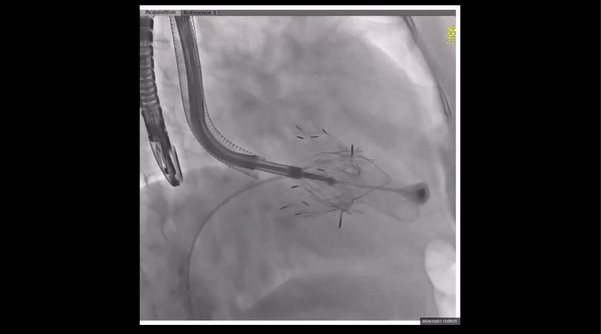

術前右室造影

夾持件位置確認

室間隔位置確認

瓣膜釋放